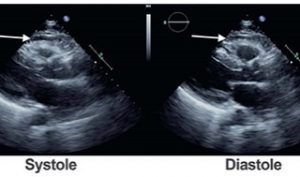

A 50-year-old patient presents following a motor vehicle accident. An echocardiogram is ordered to evaluate for shortness of breath. What is indicated by the arrow in the image?

The arrow indicates a space anterior to the right ventricle, which is of mixed echogenicity. This is a typical finding in individuals with epicardial fat. Epicardial fat is generally seen in between the right ventricular wall and chest wall. It is an area that is almost echo-free and moves with the right ventricle. CT scan of the same patient clearly delineates this structure as epicardial fat due to its low Hounsfield units (dark appearance). A pericardial effusion is usually echo-free, although a pericardial hematoma can have mixed echogenicity